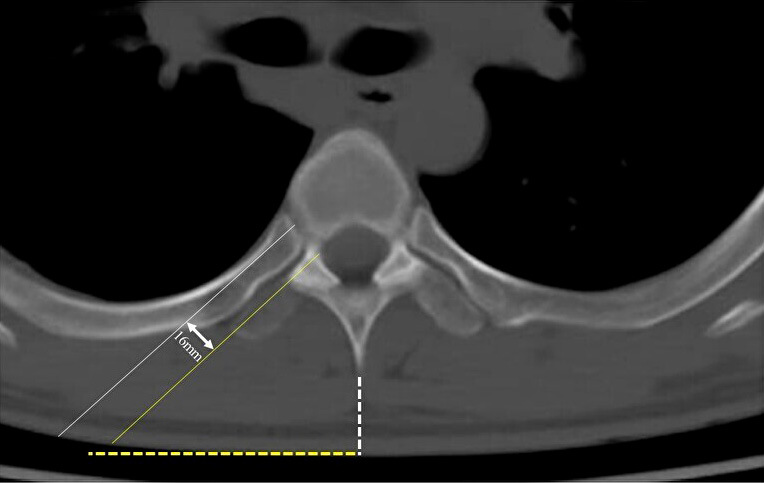

Technical note: The patient was operated in a prone position under general anesthesia. At a preoperatively determined distance from the midline, an 18-mm-long longitudinal incision was conducted, and using a 25-degree microendoscope, the operation was carried out. The endoscope was placed at an inward angle of approximately 50 degrees in the vertical direction. The ribs adjacent to the disc were identified, and the disc was exposed by resecting the ribs using a surgical high-speed drill while preserving the cortical bone of the ribs on the pleural side. The herniation was identified by drilling the ventral side of the disc and was then successfully removed. After discectomy, the dura mater expanded ventrally. Three male patients (mean age, 47.3 years) were treated, with 20 weeks of follow-up on average, 237.7-min mean operative time, and 26.7-mL mean blood loss. The average preoperative modified Japanese Orthopedic Association score was 5.2/11, which improved to 9.5/11 postoperatively, with a 75.6% average recovery rate. The 10-s step test score improved from an average of eight times preoperatively to 20 times postoperatively. No serious perioperative or postoperative complications or residual rib pain were observed.

Conclusions: The proposed TCMED approach for treating central TDH that causes myelopathy allows for safe access to the level of the posterior vertebral wall using the rib as a landmark for resecting the rib head without opening the chest. Using the angled microendoscope and curved surgical instruments, the central TDH, located ventral to the spinal canal, can then be safely and effectively resected without spinal cord retraction.